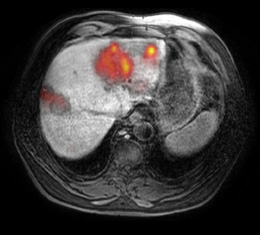

Die Größe der durch einen Dickdarmkrebs gebildeten Lebermetastase ist entscheidend, ob von dieser Metastase Tumorzellen in die Blutbahn gestreut werden. Das würde für eine engmaschige Überwachung und eine eventuelle Chemotherapie nach der Operation sprechen.

Durch Blutentnahmen während der Operation konnten die Dresdner Ärzte unter der Leitung von Klinikdirektor Prof. Dr. Jürgen Weitz in Kooperation mit Heidelberger Kollegen in ihrer aktuellen Studie bei über 100 Patienten die Anzahl von frei zirkulierenden Tumorzellen vor und nach dem Durchfluss der Leber in Pfortader und Lebervene ermitteln. So konnten sie aufzeigen, dass die Lebermetastasen selbst intakte Tumorzellen freisetzen, die ihrerseits auch Fähigkeiten einer metastasierenden Tumorzelle besitzen, und somit möglicherweise zur weiteren Metastasierung des ursprünglichen Darmkrebses beitragen können. Dabei entdeckten die Wissenschaftler auch einen Zusammenhang zwischen der Größe der Metastasen und dem Nachweis freigesetzter Tumorzellen.